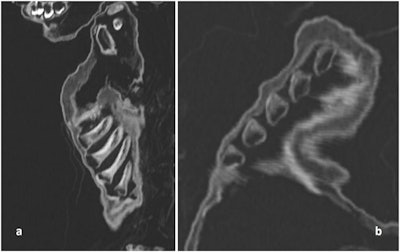

The child's soft tissue showed that he was overweight for his age. But his ribs had a malformation pattern called rachitic rosary, which is often caused by rickets or scurvy.

CT also showed pleural adhesions in the baby's right lung, suggesting that he had pneumonia -- an illness to which children suffering from rickets are more vulnerable -- and which may have contributed to his death, the team noted.